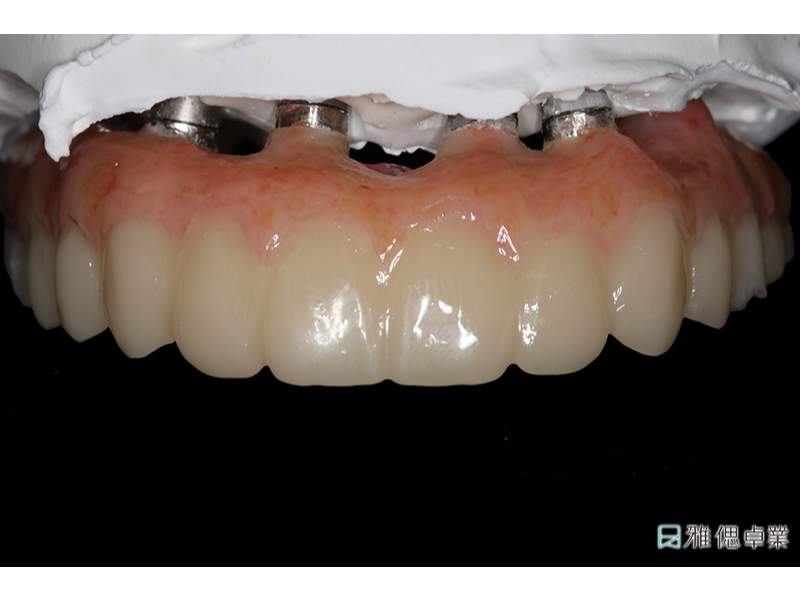

臨時假牙模型上顎

假牙模型上顎

All on 6正式假牙(上顎)